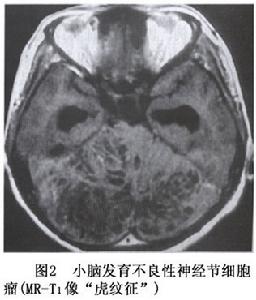

小腦發育不良性神經節細胞瘤CT為低密度或低與等密度相交替的混雜密度可累及一側小腦半球,偶有鈣化,有輕度占位效應,可幕上腦室擴大及四腦室輕度移位。MRI可見小腦半球異常增大,腫瘤無明顯占位效應,T1像為沿小腦溝排列的低信號和等信號的分層結構T2像為高信號和等信號交錯形成“虎紋征”(圖2,3)。注藥無強化。